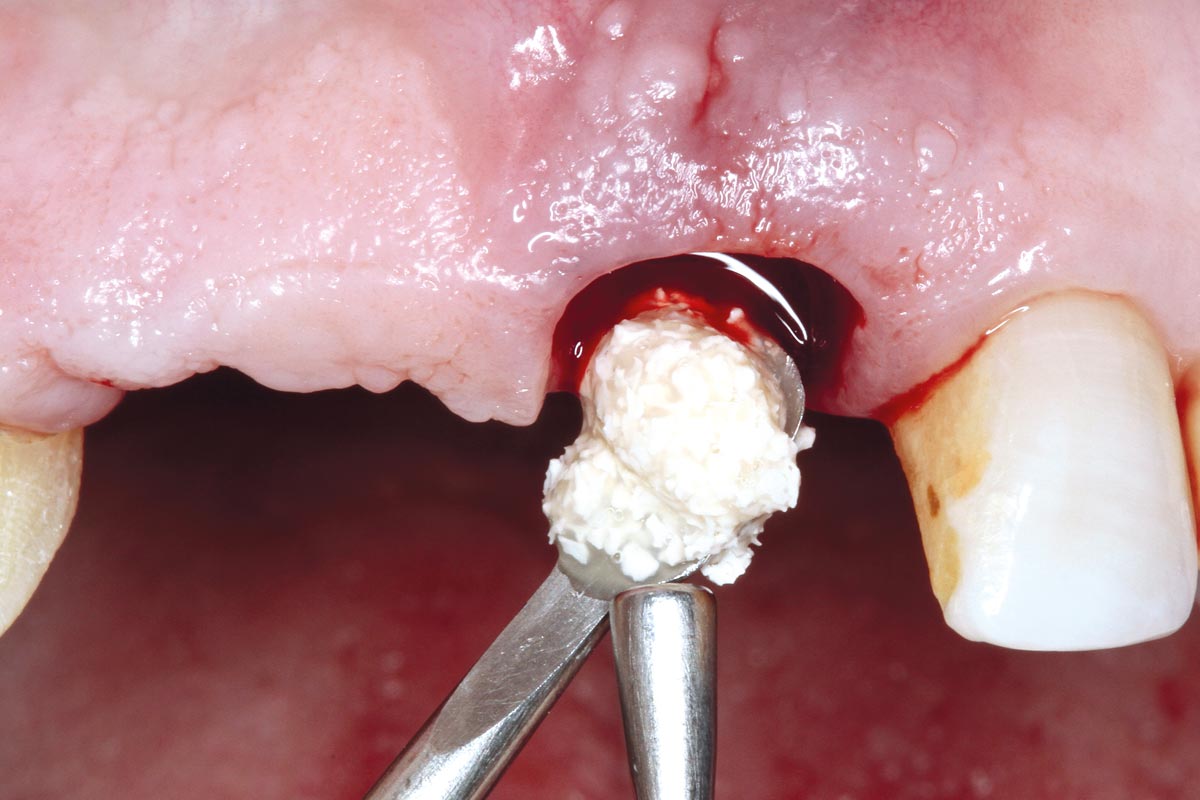

05/17 - Small cerabone® granules.

Socket preservation using cerabone® and Straumann® Emdogain® - Dr. S. Pelekanos